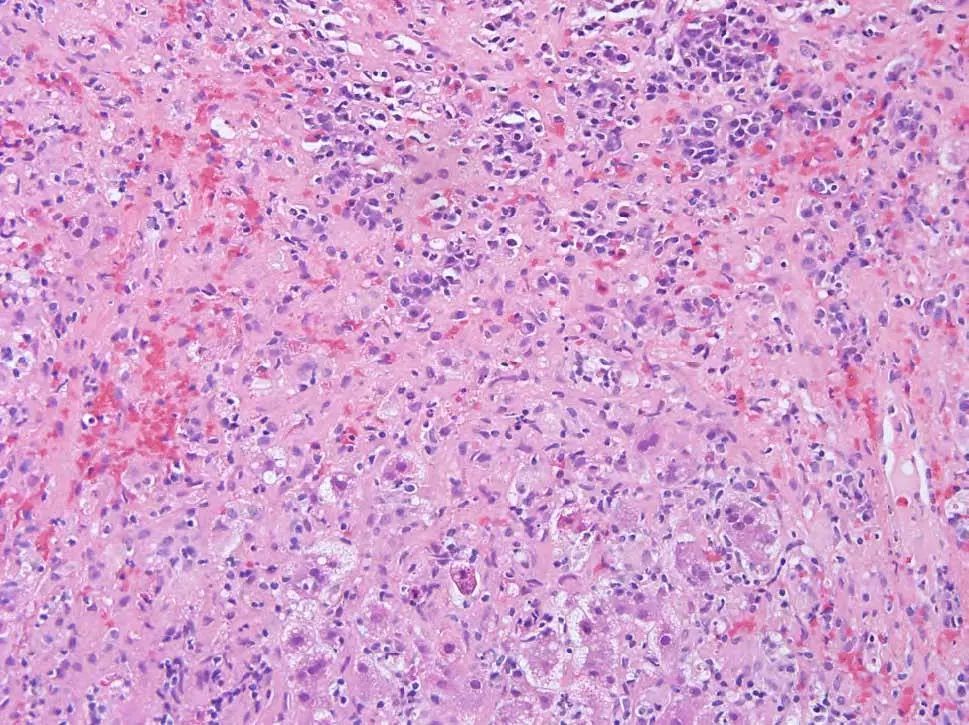

行肝活检,病理检查显示局灶性桥接或融合性坏死,伴有肝细胞脱落、凋亡(图2),易见成片浆细胞(图3)。

图2 患者病理切片示局灶性桥接或融合性坏死